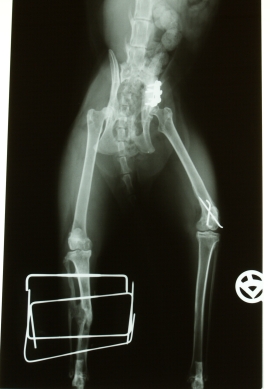

Das Einfangen ging fast problemlos, zu großem Wiederstand war die kleine nicht mehr fähig. Ein Anruf bei meiner Haustierärztin, die ihren eigenen Feiertagsplan fast selbstverständlich über den Haufen warf (an dieser Stelle nochmal ein ganz dickes Dankeschön !!), und ab ging es in die Praxis. Beide Hinterbeine waren gebrochen: das eine glatt in den Nähe des Kniegelenks, beim anderen war der Unterschenkel ein Trümmerhaufen. Und auch im Becken knirschte es...

Der glatte Bruch wurde mit Draht gespickt, der Trümmerbruch mit einem Fixateur extern versorgt und ins Becken kam eine Miniplatte. Alle OPs wurden gut überstanden und ihren neuen Namen "Kohle" bekam die kleine spontan, als die Rechnungen sich aufsummierten.